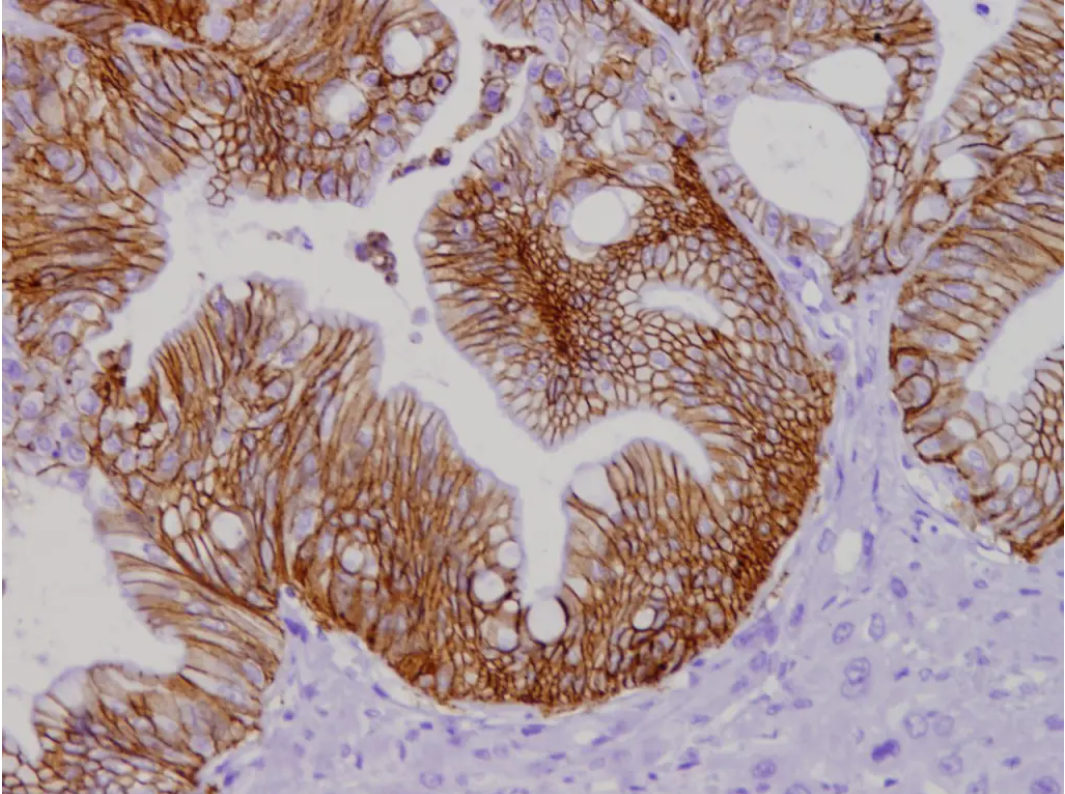

Luego de realizar experimentos con organoides —modelos celulares cultivados en laboratorio a partir de pacientes— y pruebas en modelos preclínicos, los investigadores confirmaron que la ausencia de esta proteína incrementa la formación de metástasis en el hígado.

Dicho esto, el estudio también identificó el papel de otra proteína, llamada claudina-2, que interviene en la unión entre células. Al bloquearla, se observó una reducción en la capacidad de las células tumorales para agruparse y propagarse.